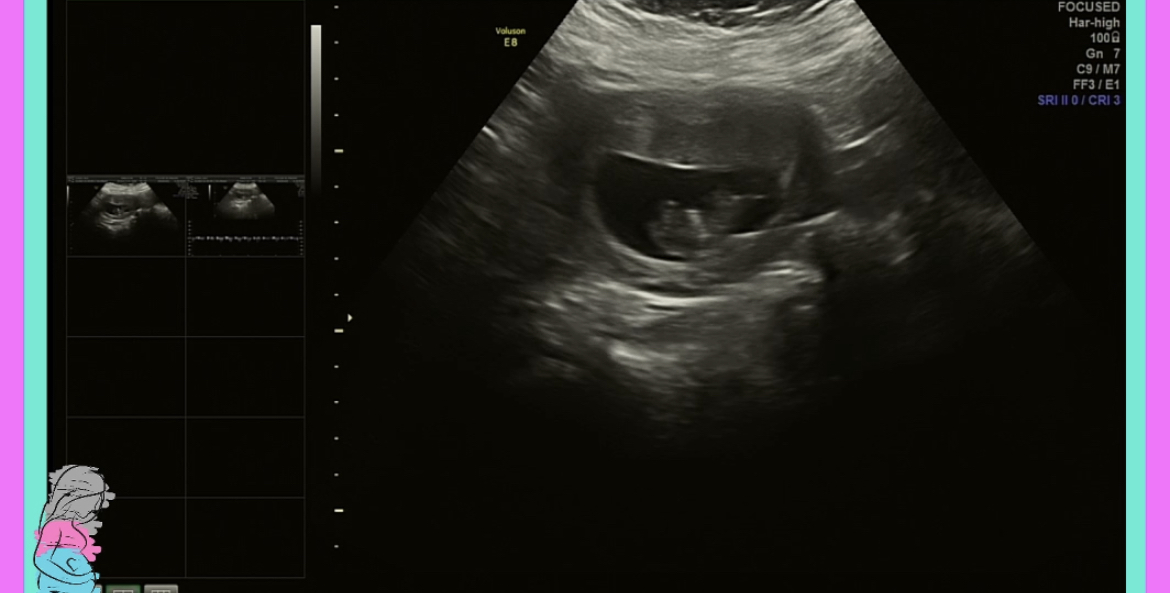

Finally!!! We got to see our little “tater tot” today!! ❤️ Baby was moving and wiggling around like crazy, measuring right at 3 cm at 9 weeks 4 days (exactly how far along I am), and heartbeat at a whopping 176 bpm. We could actually see the heart flutters!!! And the punches and kicks!!!! I can tell already my bladder will get a beating in the 3rd trimester. 😅 I can’t even express my gratitude and relief to see and hear a perfectly healthy little baby in there. 🥰